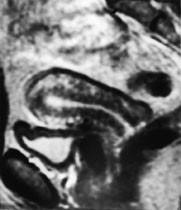

T2-vektede bilder fremstiller tre soner i corpus uteri (fig 11). Den indre sonen (endometriet) har meget høyt signal, mens den ytre sonen (myometriet) har middels høyt signal. Overgangssonen mellom disse fremtrer som et bånd med lavt signal. Den representerer den innerste delen av myometriet, der cellene ligger tett sammenpakket med sparsom ekstracellulær matriks (14). Utseendet til corpus uteri varierer med fasen i menstruasjonssyklus og med andre hormonelle stimuli.

Cancer cervicis uteri

Tumor fremstilles tydelig på T2-vektede bilder (fig 12). Størrelsen er den viktigste faktor for prognosen, og MR gir god informasjon om denne (15). MR kan dertil påvise infiltrasjon til parametrier, bekkenvegg, blære og rectum samt affeksjon av urinledere. Siden den kliniske stadieinndelingen er usikker, har MR stor betydning i primærutredningen, spesielt ved store svulster.